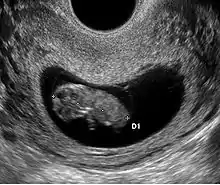

Embryon à 8 semaines

L'embryon mesure entre 15 et 22 mm. La vésicule vitelline qui le nourrit est juste à côté. À la fin de cette semaine, les coudes deviennent visibles